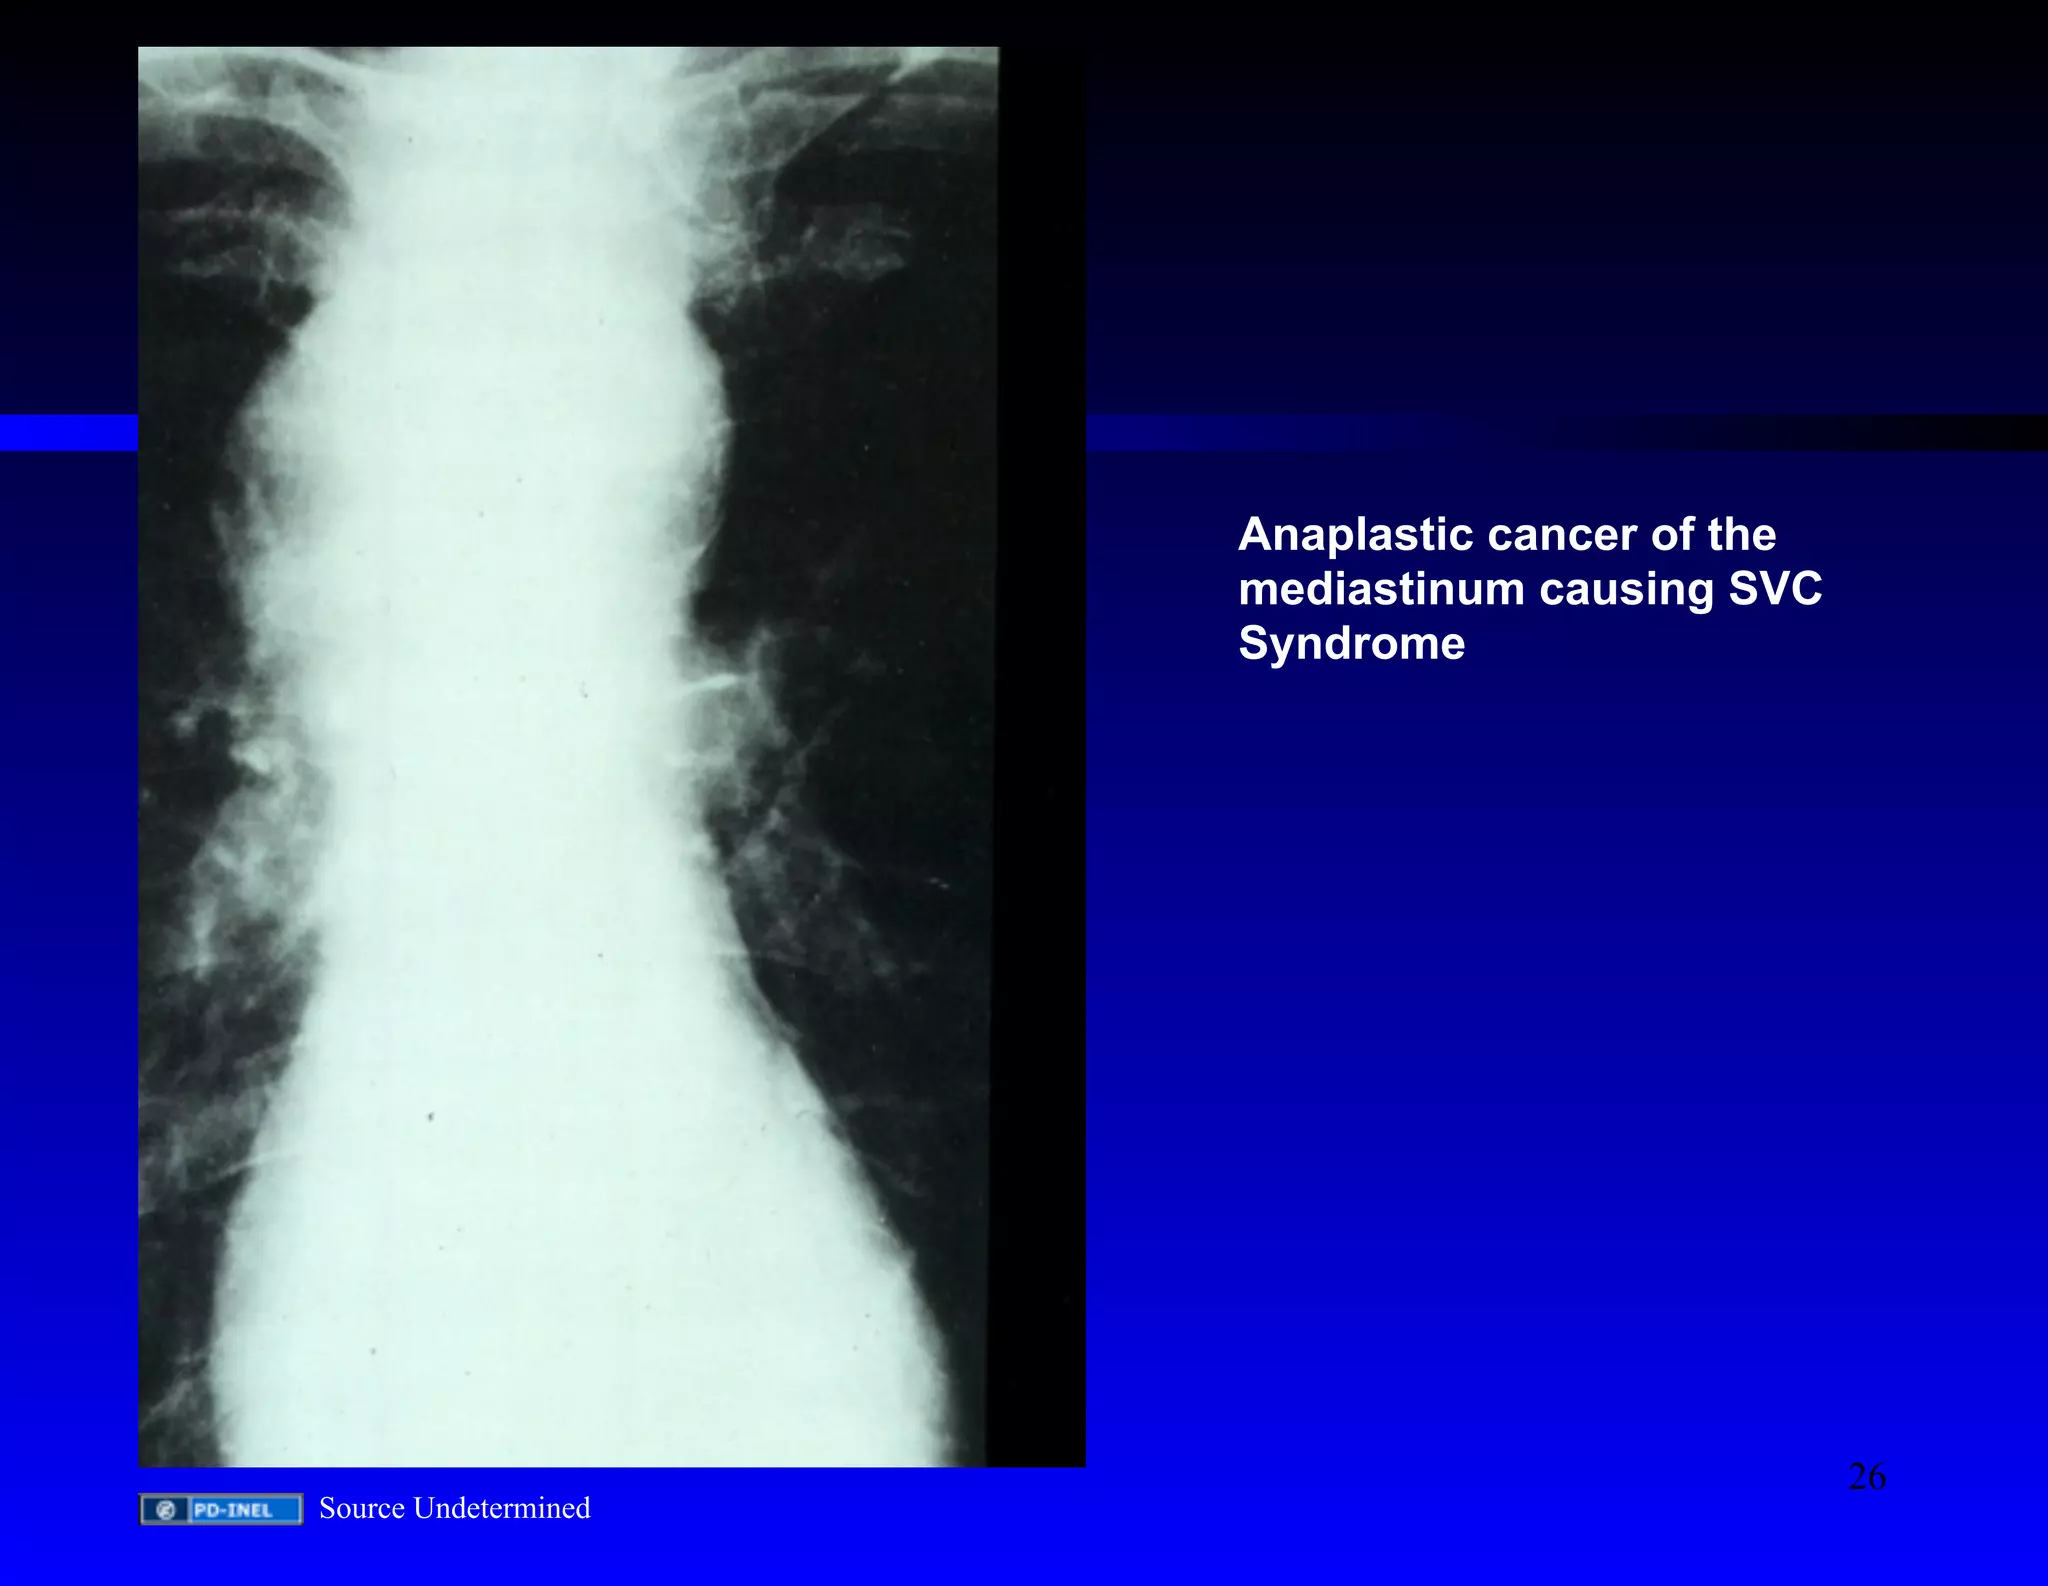

Anaplastic cancer of the

mediastinum causing SVC

Syndrome

Source Undetermined